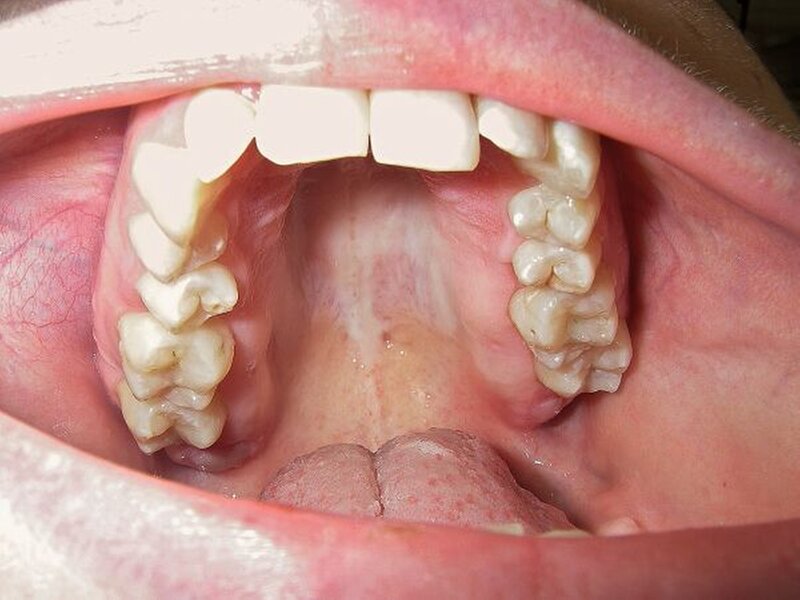

Eine 25-jährige Patientin (ehemalige Raucherin) stellte sich erstmals im vierten Quartal 2008 in unserer Praxis zur zahnärztlichen Kontrolle vor. Es imponierte eine beidseitige Schwellung des Zahnfleisches im Oberkiefer palatinal vom zweiten Prämolaren bis zum dritten Molaren. Das Zahnfleisch blutete stark bei nur leichter Sondierung (Gingivaler Blutungsindex 65 Prozent). Die Mundhygiene war verbesserungsbedürftig (Plaque Control Record 50 Prozent). Die Patientin gab an, dass die Schwellung des Zahnfleisches innerhalb der letzten drei Jahre zugenommen und nun eine Größe angenommen hat, die die Patientin subjektiv stört. Eine familiäre Häufung dieser Zahnfleischschwellung konnte von der Patientin nicht bestätigt werden. Nach einer ausführlichen Hygienisierungsphase und Motivation wurde die Diagnose einer (hereditären) gingivalen Fibromatose in Verbindung mit einer generalisiert moderaten, lokalisiert schweren chronischen Parodontitis gestellt (BOP 83 Prozent). Diese Diagnose wurde freundlicherweise von Professor Dr. Thomas Hoffmann, Dresden, bestätigt. Als weitere Diagnosen wurden ein Tiefbiss mit Deckbisscharakter (Distalbisslage) sowie eine Aplasie des Zahnes 34 mit vollständigem Lückenschluss gestellt. Ebenfalls fand sich ein für PA-Patienten typischer Foetor ex ore. Die Weisheitszähne im Unterkiefer waren im distalen Bereich von einer Schleimhautkapuze bedeckt, so dass sich eine Pericoronitis manifestiert hatte. An den Palatinal- flächen der Weisheitszähne des Oberkiefers kam es durch die Fibromatose zu einer Ausbildung von Pseudotaschen von sieben Millimetern Tiefe. Die Fibromatose wies insgesamt eine sehr weiche und verschiebliche Konsistenz auf.

Eine medikamentös bedingte Ursache im Sinne einer Gingivahyperplasie konnte ausgeschlossen werden. Ebenso erwies sich ein erhöhter Nüchternblutzuckerwert von 121 Milligramm pro Deziliter als möglicher Parodontitis-Co-Faktor nach Abklärung des HbA1c-Wertes als nicht wahrscheinlich. Die bei der Entfernung der oberen Weisheitszähne verursachte Mund-Antrum-Verbindung wurde durch Schwenkung und Dehnung der Fibromatose verschlossen. Die Zähne 38 und 48 wurden ebenfalls entfernt. Die subgingivale Instrumentation (SRP) erfolgte in zwei Sitzungen im Sinne einer Full-Mouth-Disinfection, danach wurde in wöchentlichem Abstand der Blutungs- und Plaqueindex kontrolliert und ein CHX-Präparat in die Taschen instilliert. Zum Zeitpunkt der Reevaluation sechs Wochen nach Scaling / Root Planing konnte erwartungsgemäss keine Remission der Fibromatose festgestellt werden. Es wurde daraufhin die Indikation eines chirurgischen Eingriffs gestellt. Nach paramarginaler Inzision circa fünf Millimeter palatinal vom Sulkus folgte eine intrakrevikuläre Inzision. Das so umschnittene Zahnfleisch wurde im Sinne einer externen Gingivektomie von distal 14/24 bis distal 17/27 entfernt. Im Anschluss wurde ein Full Flap präpariert, der mit einer internen Gingivektomie ausgedünnt wurde. Im dorsalen Bereich wurde eine Tuberplastik in Verbindung mit einer distalen Keilexzsion durchgeführt, so dass eine harmonische Rekonturierung des Zahnfleisches mit Entfernung der Pseudotaschen erreicht werden konnte. Der primäre Wundverschluss wurde mit Einzelknopfnähten erzielt, das gesamte Operationsgebiet im Anschluss mit einer Verbandsplatte abgedeckt. Zwei Wochen postoperativ wurde im Bereich beider Tubera mithilfe des Elektrotoms der Zahnfleischverlauf nochmals korrigiert. Die Patientin war trotz des Umfangs des Eingriffs zu jeder Zeit beschwerdefrei. Das Recallintervall beträgt nach endgültiger parodontaler Risikostratifizierung drei Monate. Der Beginn der notwendigen kieferorthopädischen Behandlung ist noch in 2010 geplant.